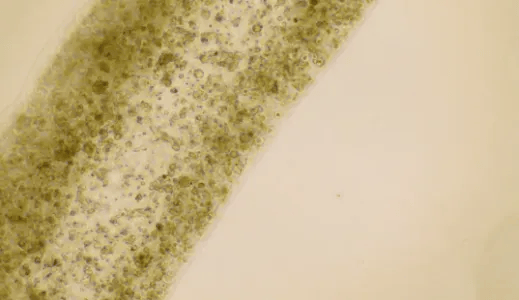

生育困境的核心难题,往往在于生殖器官的不可逆损伤。卵巢早衰、子宫内膜损伤、宫腔粘连等病症,曾是生殖医学领域的“不治之症”。传统治疗手段如激素替代、促排卵等,仅能缓解症状却无法修复受损组织。而干细胞的独特再生能力,为解决这一难题提供了全新思路。其通过定向分化替代受损细胞、分泌生长因子调节微环境、促进血管新生等多重机制,精准修复生殖系统损伤,从根源上恢复生育功能。

临床实践中的一个个奇迹,印证着干细胞疗法的实力。39岁的左女士因卵巢储备功能减退陷入不孕绝境,在接受新型干细胞囊泡技术治疗后,成功诞下健康宝宝,这一突破让卵巢功能障碍治疗迎来新曙光。更有42岁绝经女性经干细胞干预后重启月经周期,重型再生障碍性贫血患者移植后卵巢功能恢复并自然受孕,这些案例都让“生育无望”的家庭重获新生。在遗传性疾病领域,干细胞疗法同样发力,通过第三代试管婴儿技术结合脐带血干细胞移植,既让健康二宝顺利诞生,又成功救治了罹患重型地贫的姐姐,让家庭重拾完整幸福。